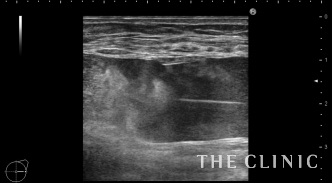

ヒアルロン酸と脂肪のしこりはベイザーで溶解して吸引、ヒアルロン酸のしこりはヒアルロニダーゼで溶解吸引しました。

吸引後の画像です。ほとんどしこりはなくなりました。